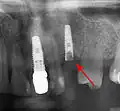

- с помощью рентгенографии изучаются качество и плотность костной ткани;